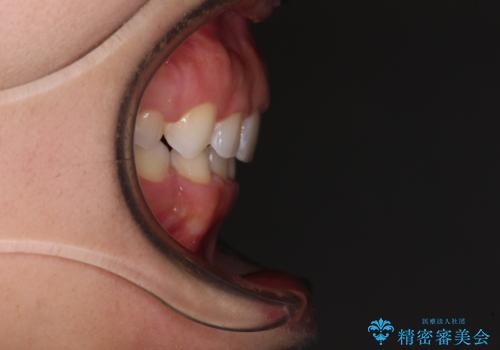

上下顎ともに前突しており、特に上顎は著しい突出感でした。

また、下顎歯列には左右差があり、非対称な抜歯が必要と判断されたため、治療は困難なものとなりました。

それでも根気強く通院してくださり、横からの顔貌の印象が大きく改善され、スムーズに口が閉じられるようになりました。